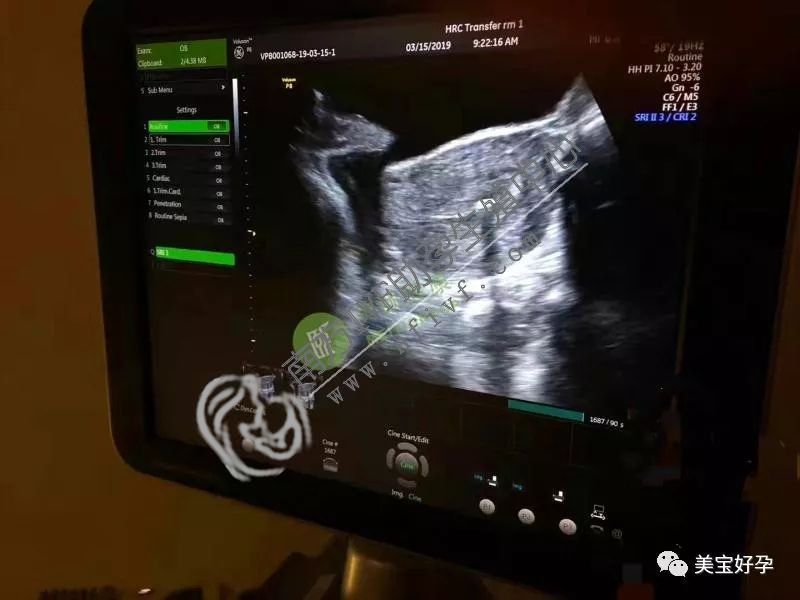

毕竟,试管婴儿仍然把胚胎直接放入子宫腔

胚胎移植后成功妊娠至妊娠前3个月,共用房间容易增加感染和刺激子宫收缩的风险

胎儿胎盘的发育仍处于不稳定状态